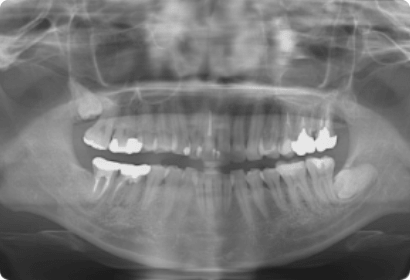

デジタルレントゲン

従来のフィルムタイプのレントゲンよりも精密で的確な診断を行うことができます

通常の診療で初めてのご来院の際は、通常こちらのレントゲンを撮影します。

デジタルレントゲンは被ばく量が少なくすみ、データも劣化せず保管できます。

また、現像液を使わないため、環境にもやさしいのがデジタルレントゲンです。